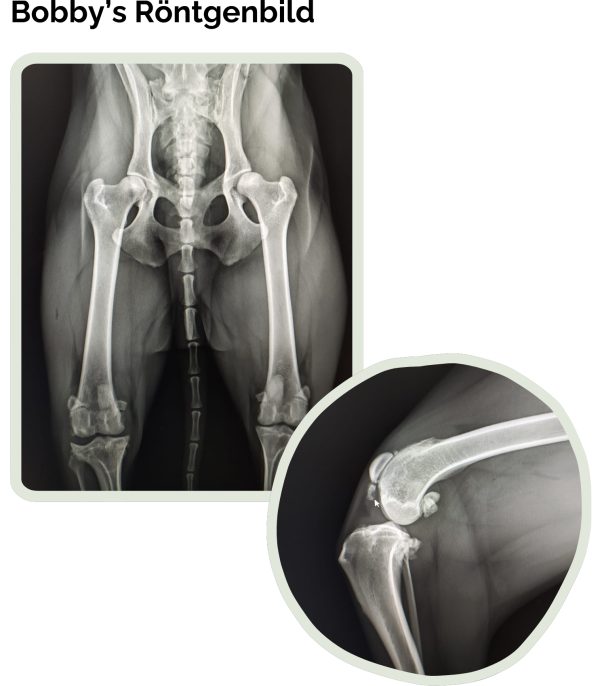

Vor kurzem begann Bobby plötzlich leicht zu humpeln. Schnell ahnten wir, dass etwas nicht mit ihm stimmt. Ein Tierarztbesuch brachte dann die erste Gewissheit: Kreuzbandriss.

Doch während des Eingriffs offenbarte sich erst das ganze Ausmaß von Bobbys Leid. Neben dem gerissenen Kreuzband, das operativ versorgt werden konnte, offenbarte sich ein Knie, das von alten, schweren Schäden gezeichnet war: eine nie behandelte Fehlstellung der Kniescheibe, ein vollständig zerstörter Meniskus, poröser Knochen und deutliche Spuren jahrelanger Fehlbelastung.

Diese Verletzungen waren nicht neu – sie erzählten von einem langen Weg voller Schmerzen, den Bobby still und allein gegangen ist.